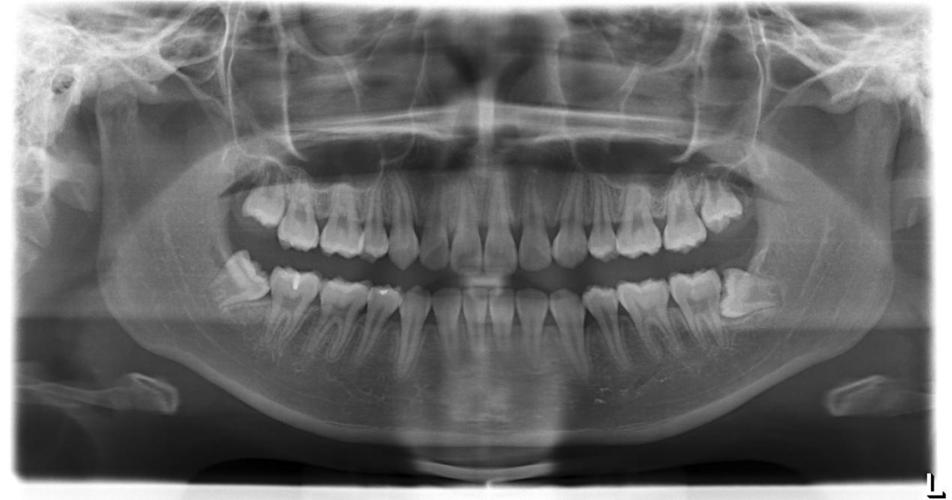

口腔全景片(OPG / Panoramic X-ray)——口腔的“全身照”

- 一句话概括: 它就像一张我们口腔的“全身照”,将上下颌骨、牙齿、牙槽骨、颌骨、上颌窦等重要结构,在一个二维平面上完整地展示出来。

- 工作原理: X球管和探测器围绕患者的头部做360°旋转,通过特殊的运动轨迹,将三维的口腔结构“展开”成一张二维图像。

- 它能告诉我们什么?(优点)

- 视野广: 一次性看全所有牙齿和颌骨的大致情况,是口腔检查的“入门级”利器。

- 操作快: 整个过程只需10-15秒,患者配合简单。

- 辐射低: 辐射剂量相对较小,约为0.02-0.05mSv,非常安全。

- 性价比高: 价格通常在100-300元之间,适合作为常规检查。

- 它的局限性在哪里?(缺点)

- 二维成像: 所有结构都重叠在一张平面上,存在放大、失真和重叠效应,两颗牙重叠在一起,可能误判为一颗;牙根的实际长度和位置可能不准。

- 细节模糊: 对于牙根尖的细微病变、骨密度的精确判断、神经血管的走行等,分辨率不足。